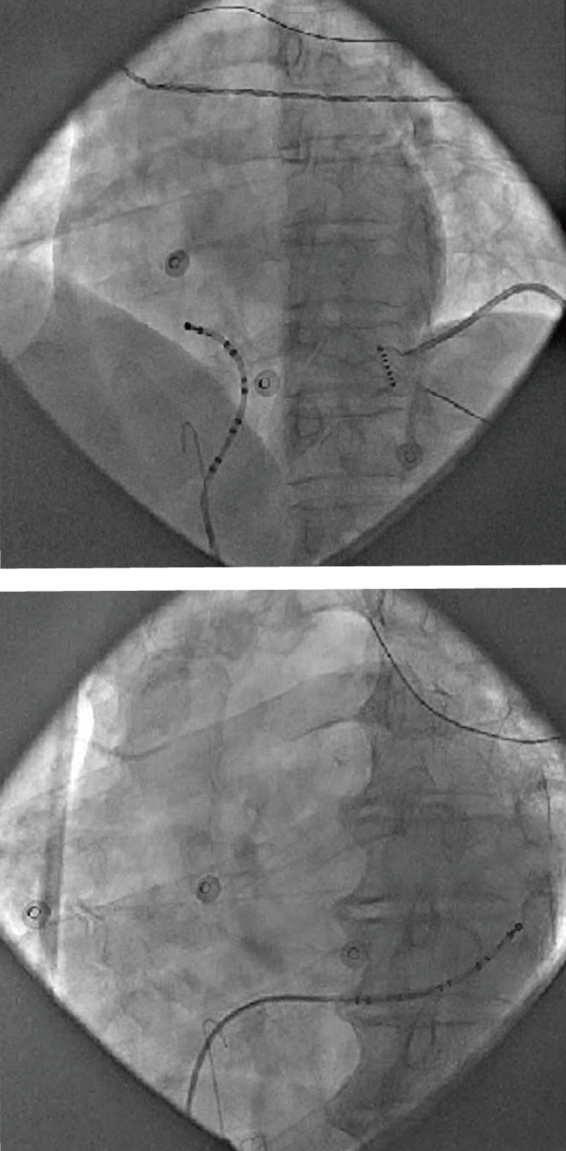

Triguy™ SinusFlex™ decapolar catheter with the patented spatial curve for easy access to Coronary Sinus Ostium (CSO) offers effective and reliable CS mapping. It significantly simplifies CS catheter placement, especially dealing with anatomical variations.